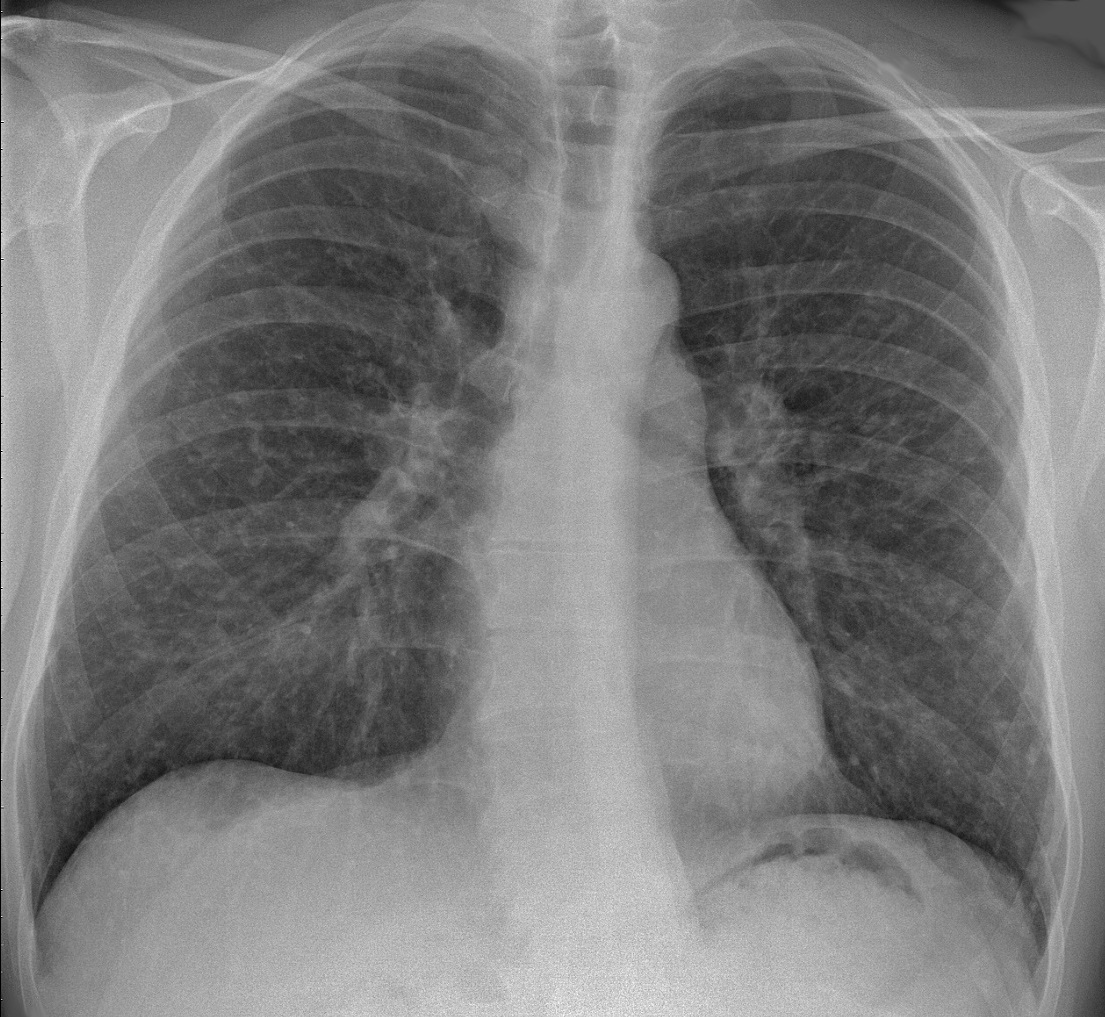

The granulomas mostly affect the hilar lymph nodes and lungs, causing restrictive lung disease.

Histology of sarcoidosis includes naked granulomas and stellate inclusions (‘asteroid bodies’) are often seen within giant cells of the granulomas.